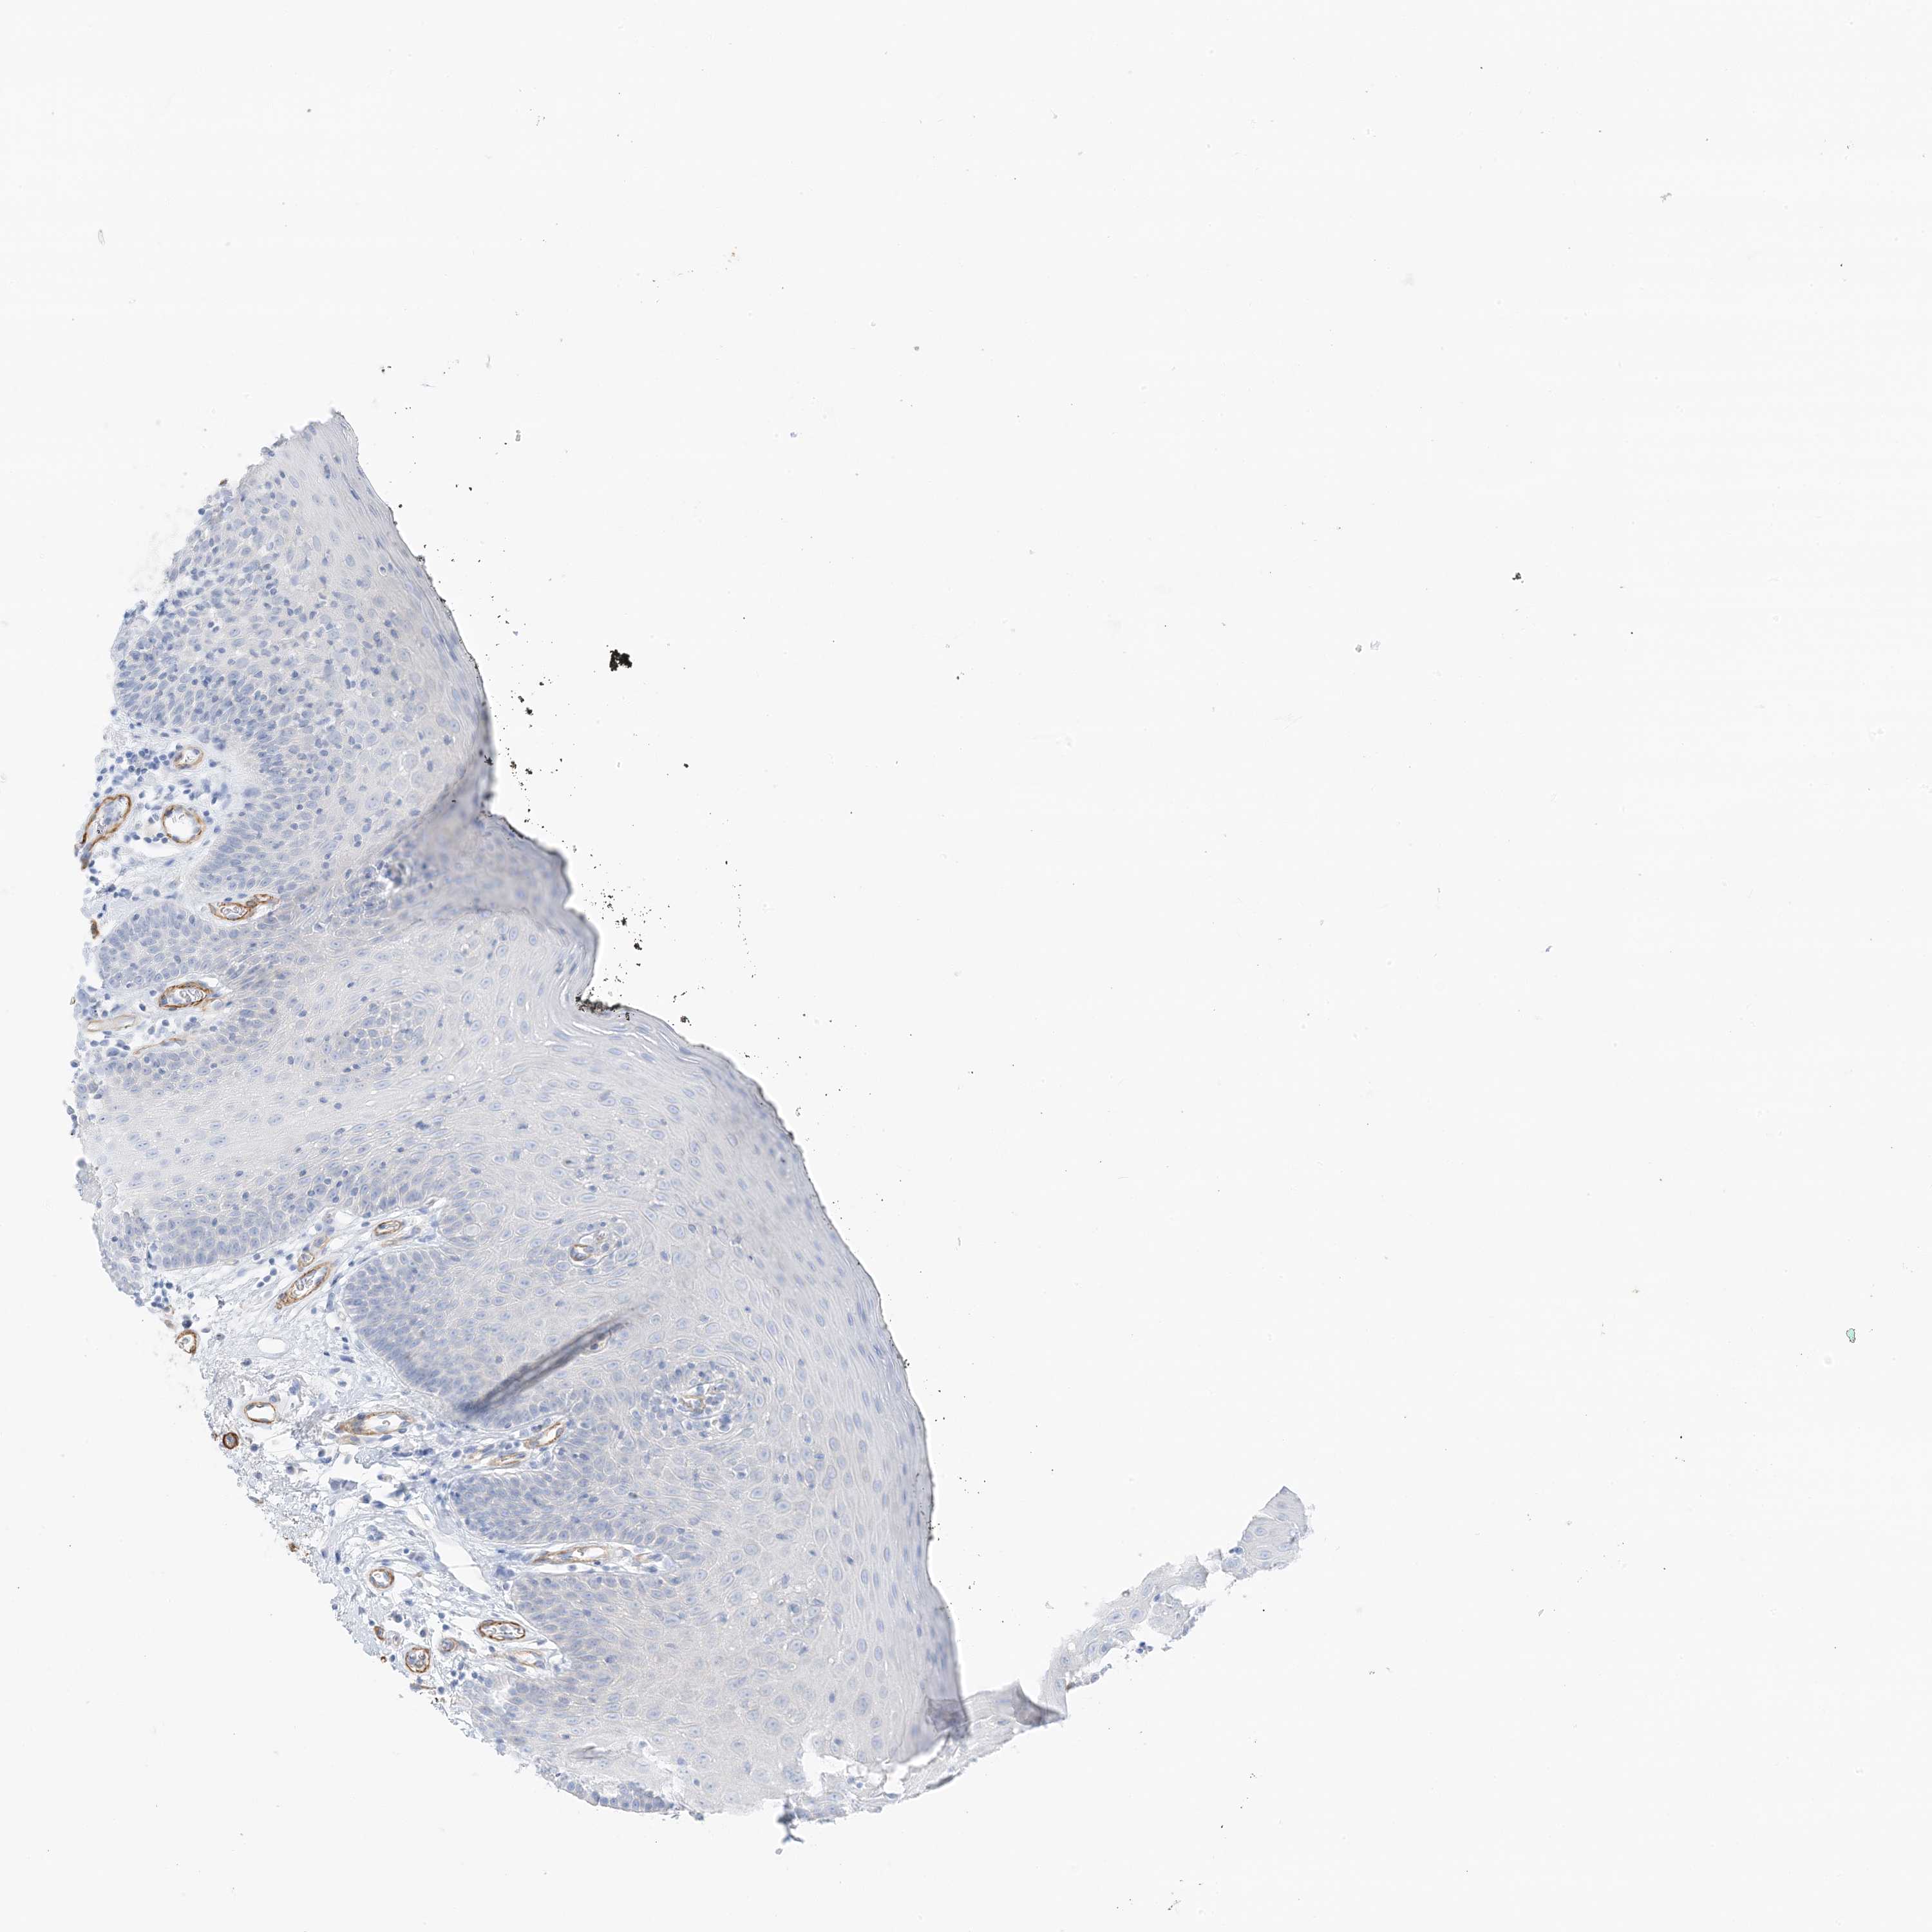

TISSUE PRIMARY DATA ORAL MUCOSA Show tissue menu

ORAL MUCOSA - Antibody stainingi

Antibody staining in the annotated cell types in the current human tissue is reported as not detected, low, medium, or high, based on conventional immunohistochemistry profiling in selected tissues. This score is based on the combination of the staining intensity and fraction of stained cells.

Each image is clickable and will lead to virtual microscopy that enables deeper exploration of all samples and also displays staining intensity scores, fraction scores and subcellular localization as well as patient and tissue information for each sample.

Antibody HPA035603Antibody HPA035962

Squamous epithelial cells Not detectedNot detected